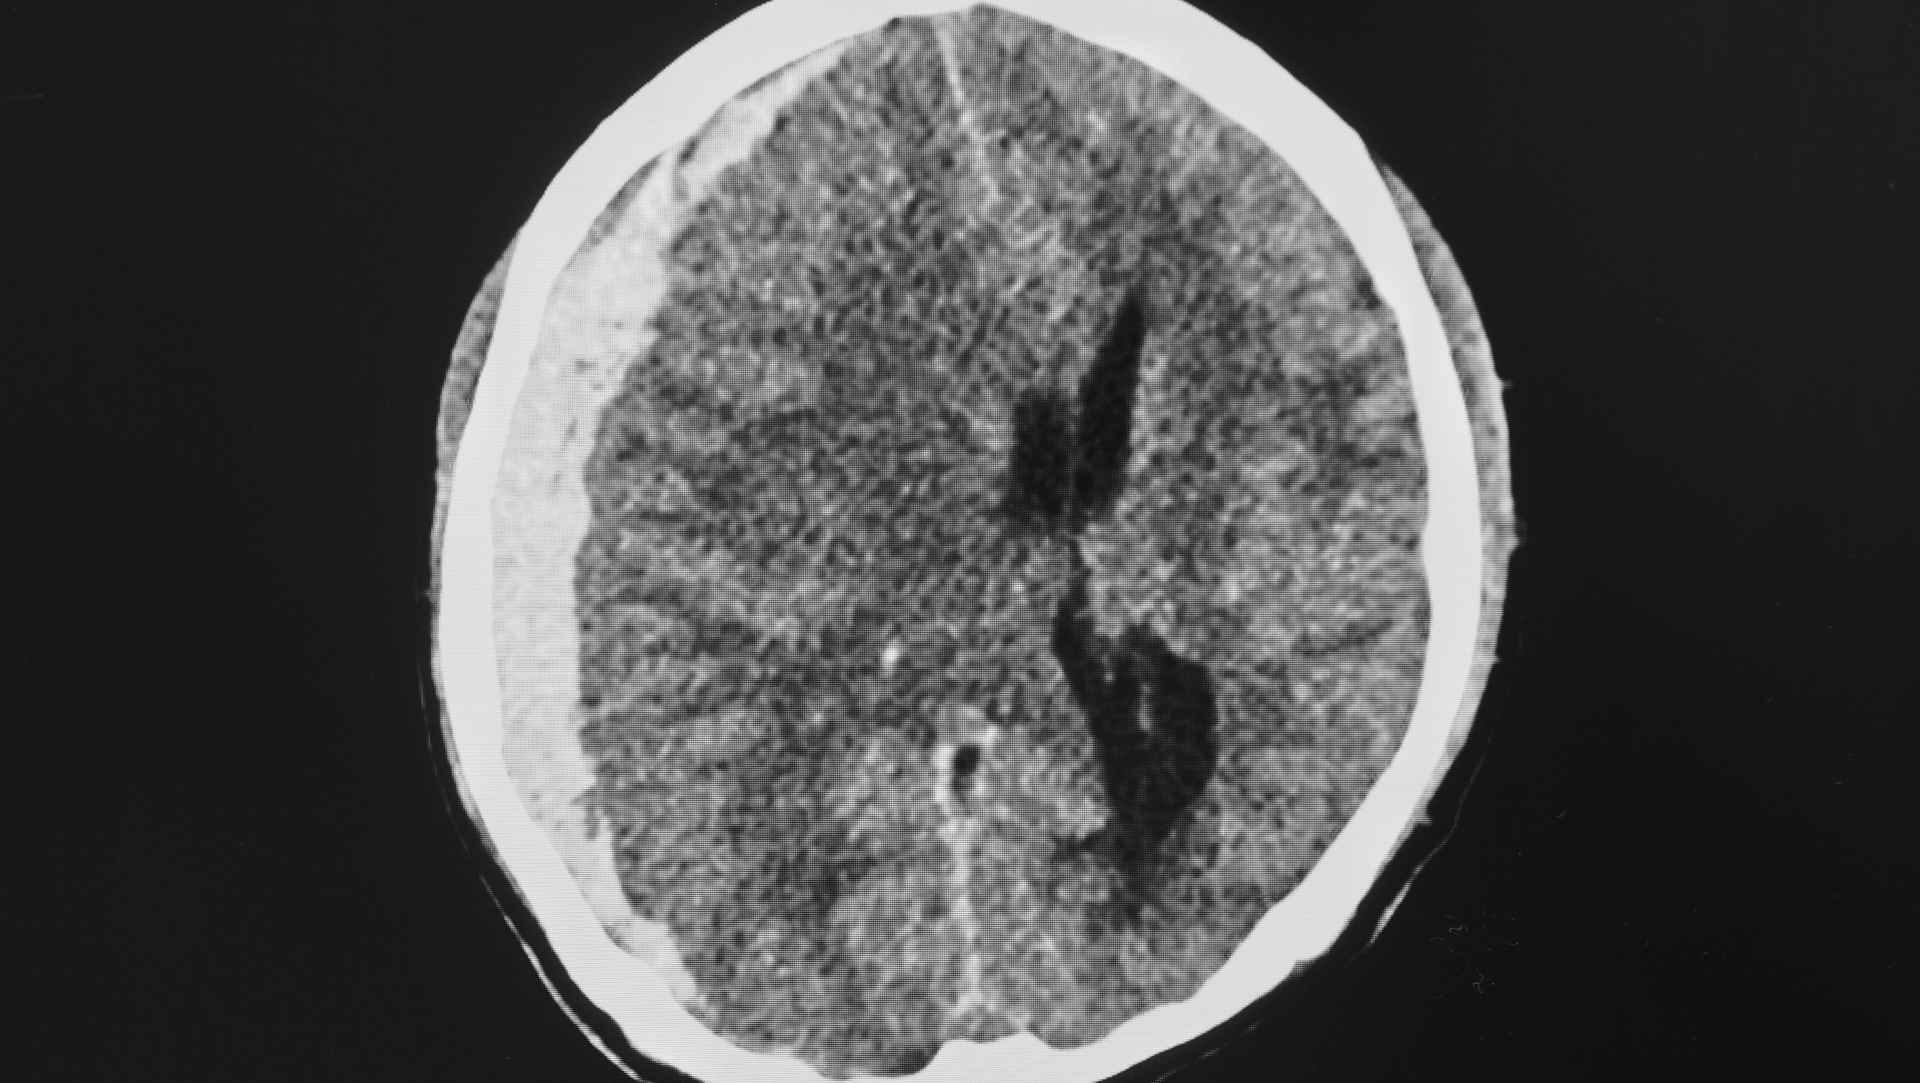

- Globally, access to ICP monitors is variable; the trialists sought evidence relevant to both high-resource and resource-limited environments where clinicians rely on neurological examination and CT imaging.

- Imaging–clinical examination strategy (Imaging–Clinical Examination Group): tiered management driven by scheduled/triggered CT imaging and neurological examination (including deterioration signals and radiological signs of raised ICP), without continuous ICP data.